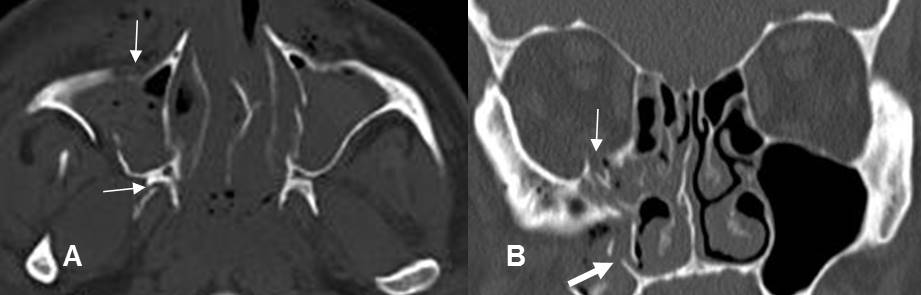

Fig 214. Fractura del arco cigomático.

A y B: TAC axial. Fracturas del arco cigomático. Lineal en A y deprimida en B.

En ambos casos hay otras fracturas asociadas de los antros maxilares.